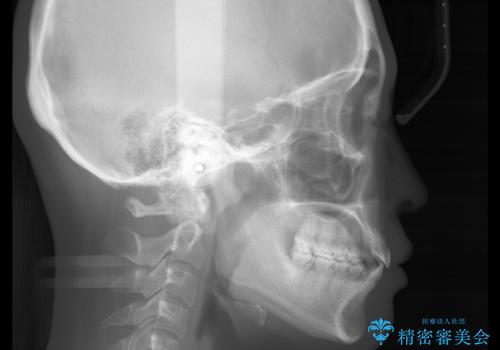

前歯で噛めない:オープンバイト(開咬)を非抜歯インビザラインで治療

- 上下の歯が噛んでいないことを気にしてご相談にいらした方です。

オープンバイトの方への治療は、通常抜歯を行いワイヤーによる矯正治療を行うことが多いですが、今回はインビザラインの特性を生かし、非抜歯にて綺麗な歯並びを作ることが出来ました。

舌癖がある方は、歯を内側から押し出す力が日常的に働くため、矯正治療後も歯と歯の隙間が開いてしまうなどの後戻りのリスクが高いことが知られています。舌の正しいポジショニングやお口周りの筋肉のトレーニングを行うことで後戻りのリスクを減らすことが可能です。